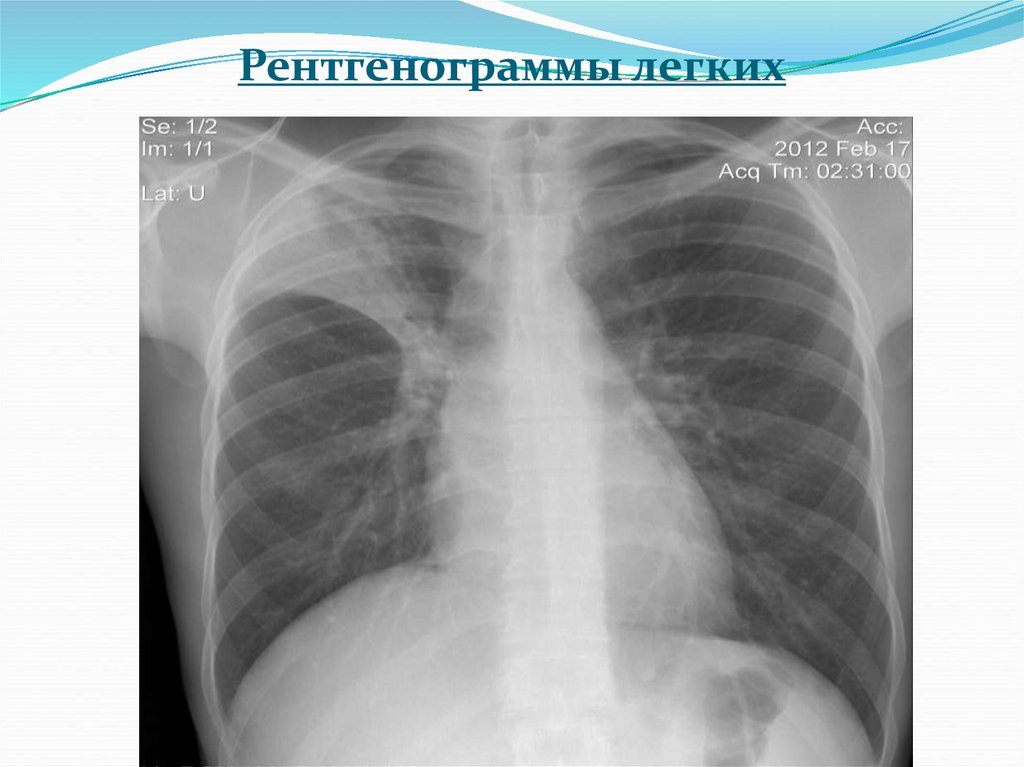

5. Рентгенограммы легких